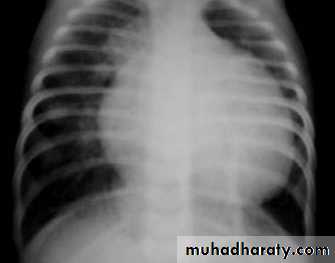

CXR : Boot-shaped normalsize heart

CXR : Egg on side & narrow mediastinum